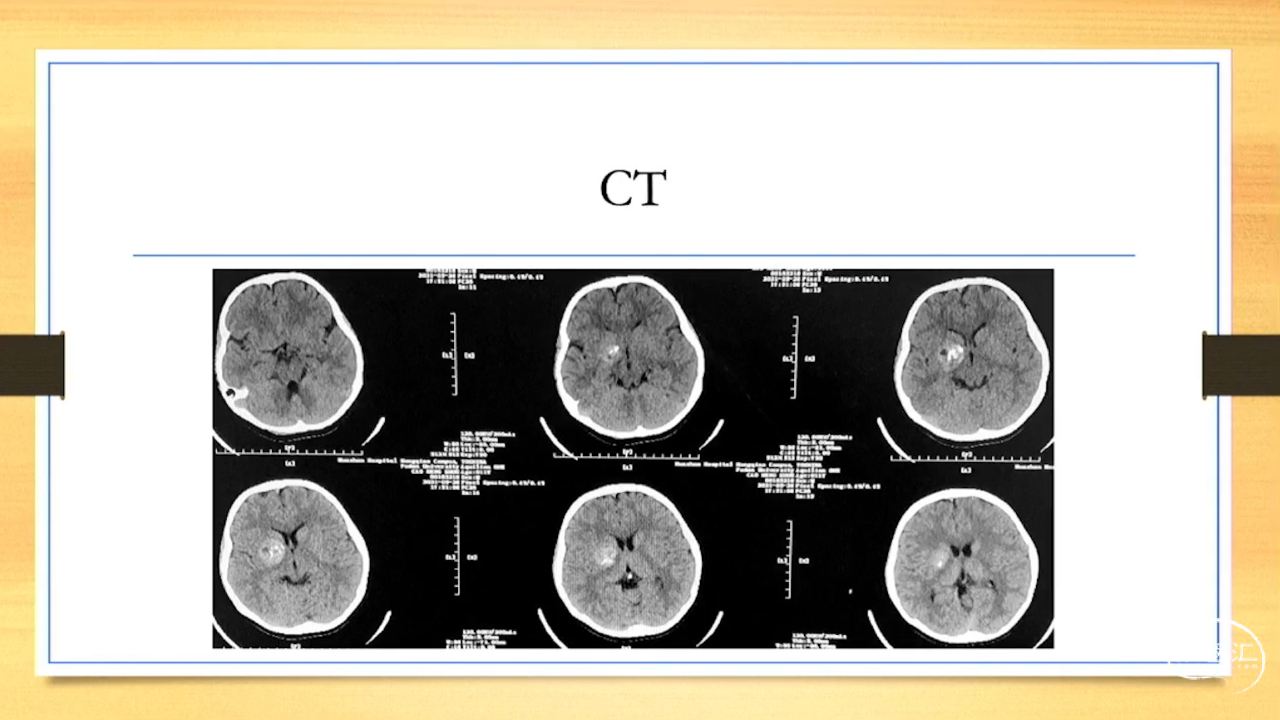

张荣教授:儿童颅内生殖细胞瘤的手术治疗

颅内生殖细胞肿瘤的治疗是手术、放疗、化疗、内分泌及其他多学科的整合治疗。及时、精准、合理的手术治疗是iGCT患者提高生存率、降低并发症、改善神经内分泌功能的关键。